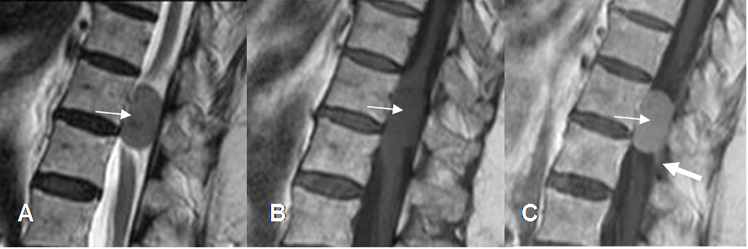

Fig 236. Ependimoma.

A: RM sagital en T1 con contraste y B: RM sagital en T2. Lesión tumoral que expande el cono medular. Muestra porción quística en la parte superior (Flechas delgadas) y porción sólida en la parte inferior. con realce heterogéneo del contraste. (Flecha gruesa). En su interior hay zona hipointensa que corresponde a hemosiderina, por sangrado antiguo.